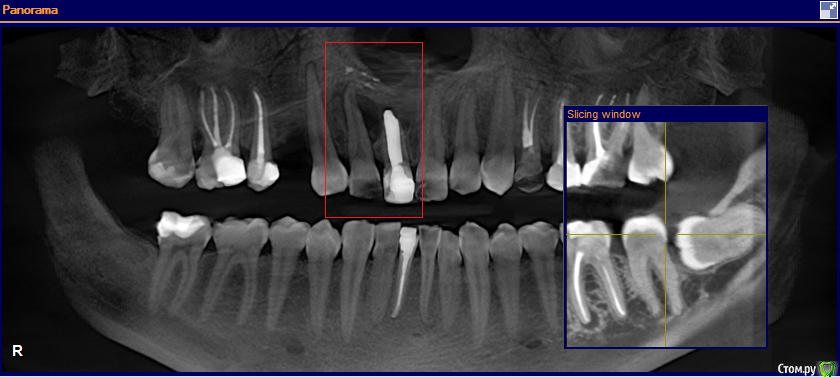

Wintermute Опубликовано 18 мая, 2016 Поделиться Опубликовано 18 мая, 2016 Обнаружили кисту и хирург говорит что нужно удалять два передних зуба, один пролеченный возможно еще в СССР (и видимо является причиной проблемы), второй здоровый, но киста видимо как-то "отъела" часть корня. У меня возникли некоторые сомнения что удаление необходимо, интернет пишет что киста лечится сейчас резекцией корня зуба, а сами зубы стараются сохранить. Может ли кто-нибудь сказать возможен ли вариант с сохранением зубов (или одного) в моем случае? Ссылка на комментарий

red_butler Опубликовано 19 мая, 2016 Поделиться Опубликовано 19 мая, 2016 Проверить 1.2 на витальность, скорее всего эндо лечение. Я бы все таки сделал цистэктокию с РВК 1.1 и ретроградным пломбированием. 1 Ссылка на комментарий

St. Опубликовано 19 мая, 2016 Поделиться Опубликовано 19 мая, 2016 Еще одно перелечивание 1.1 не переживет, там от стенок и так мало осталось и по ширине и по длине. Я бы за него не боролась.У 1.2 шансов больше, но смущает его резорбция, за него если есть желание ещё можно побороться.Если готовы попробовать и найдете доктора можно попытаться. Само собой лечение будет негарантийным и достаточно дорогим, хотя есть шанс на успех.Если хотите гарантий - то терапевт вам не помощник. 2 Ссылка на комментарий